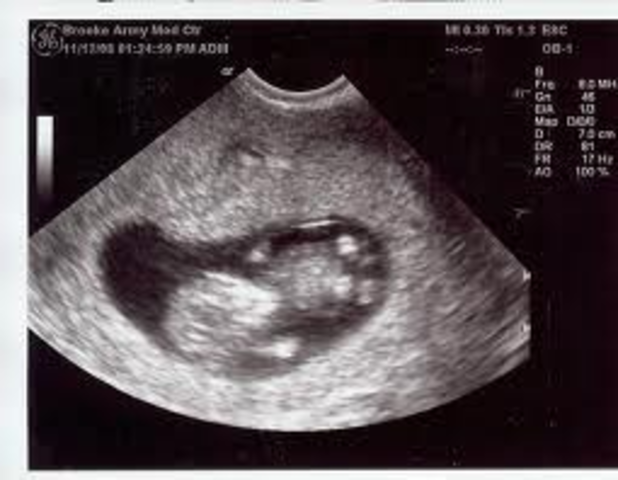

After 10 weeks the mother can have her first ultrasound.

-